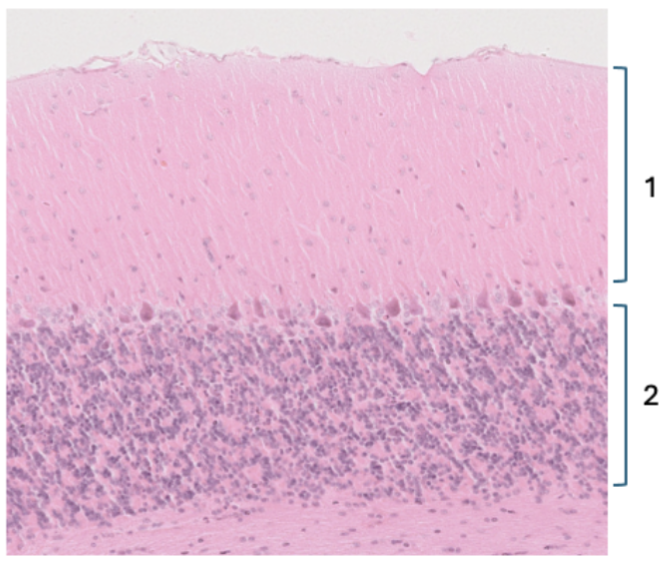

Purkinjecellernas dendriter Korncellernas cellkärnor 2 stjärncellernas cellkärnor